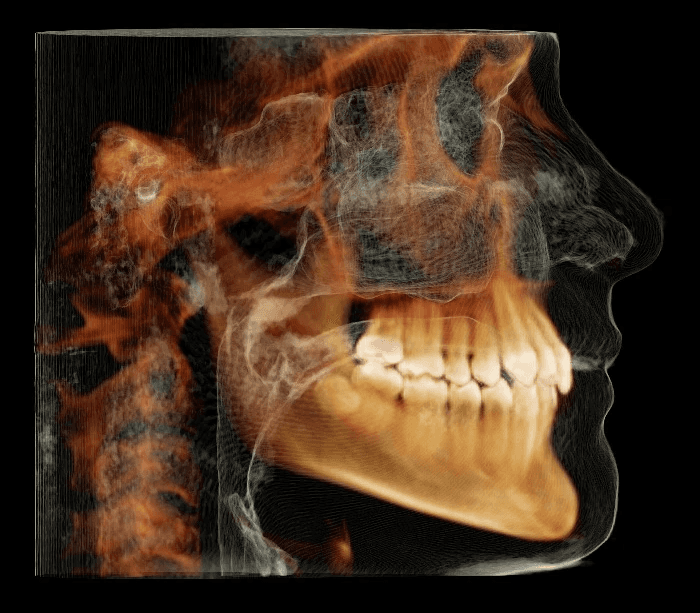

Initial treatment

X-RAYS